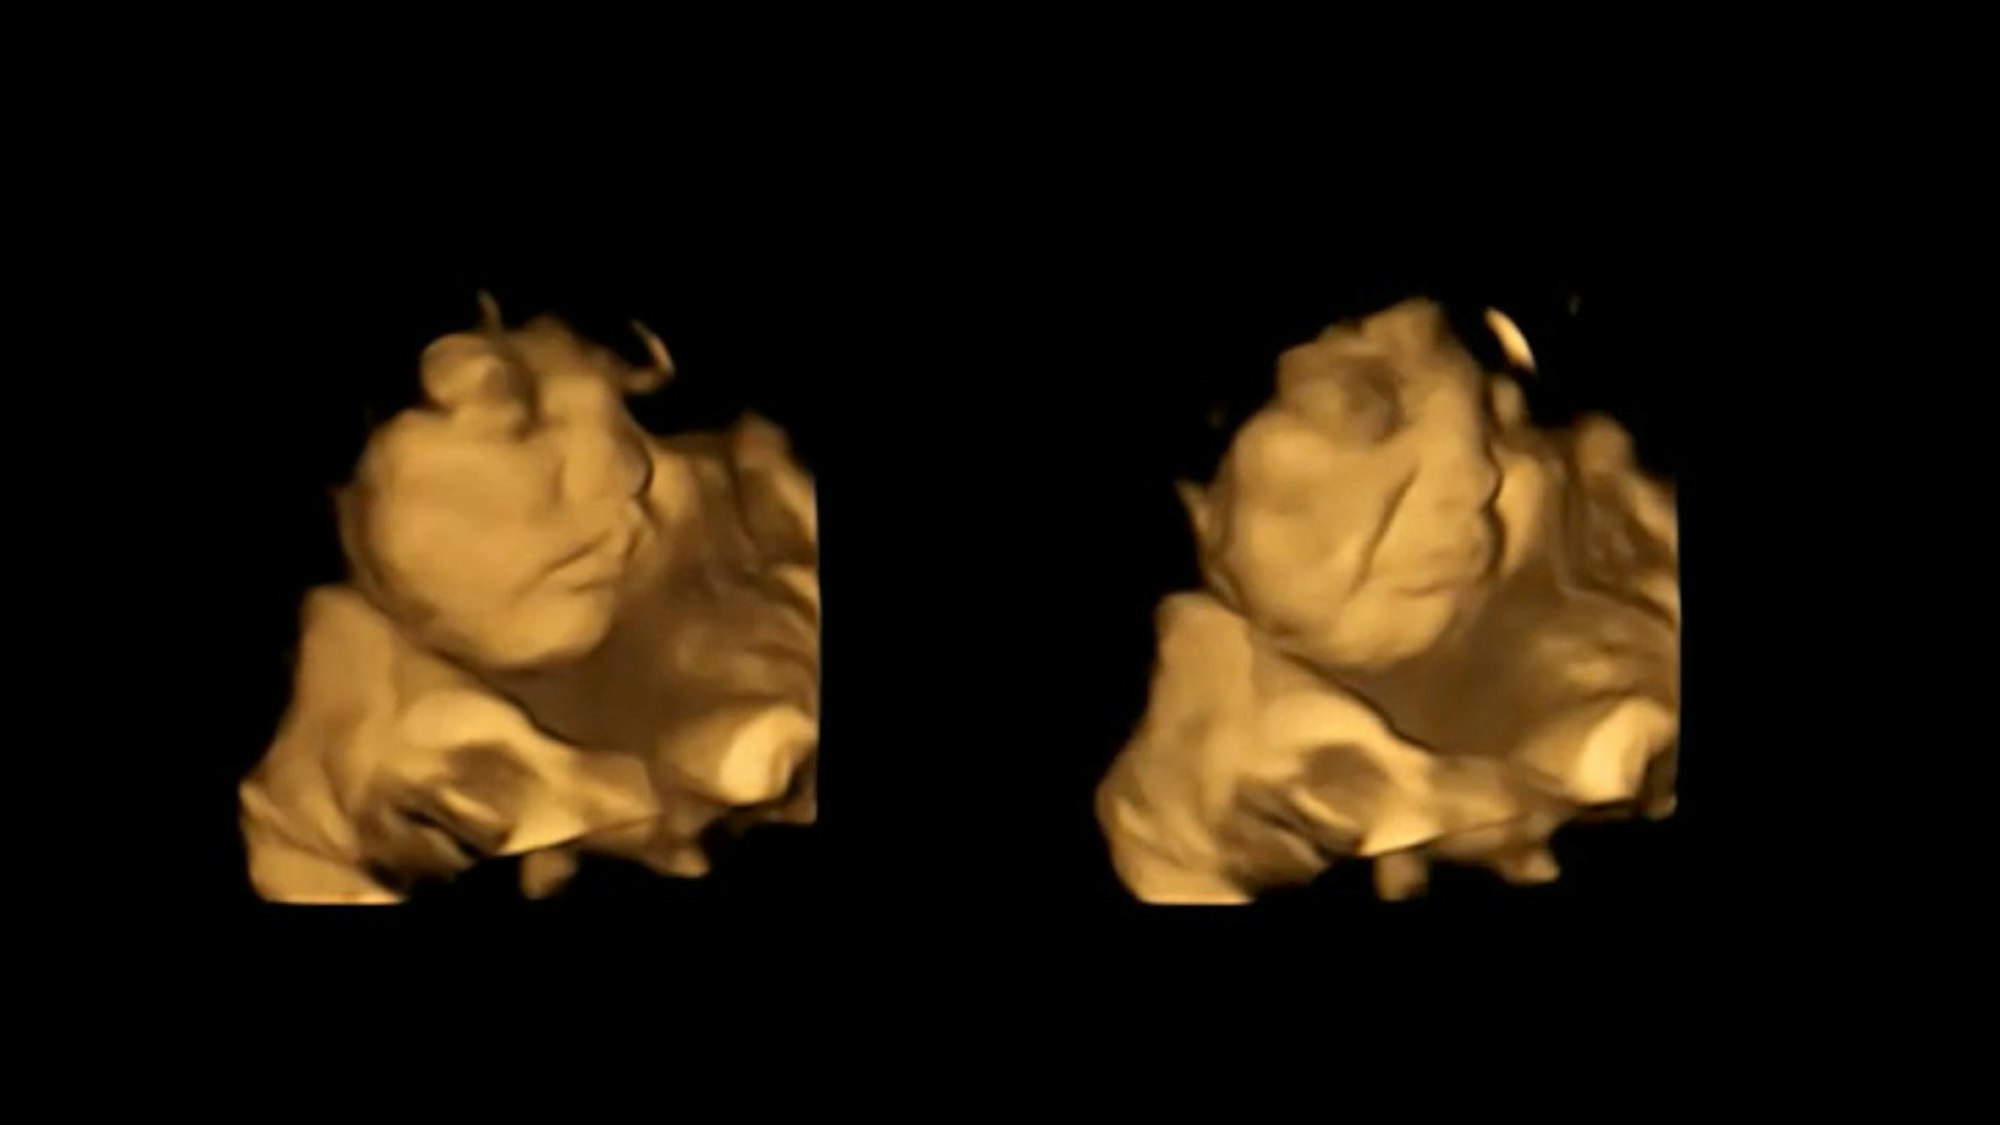

Ein Fötus mit neutralem Gesichtsausdruck (l) und der gleiche Fötus mit „Cry-Face-Reaktion“, nachdem er Grünkohlgeschmack ausgesetzt wurde (r, 4D-Scan-Bild).

Copyright: dpa/FETAP Study/Fetal and Neonatal Research Lab/Durham University

Dass Babys mit Abneigung auf Kohl reagieren, war bekannt. Es seien nun aber erstmals Beweise dafür gefunden worden, dass sogar Föten im Mutterleib unterschiedlich auf verschiedene Gerüche und Geschmäcker reagierten, heißt es in der Studie. Vermutlich entwickeln die Föten demnach Geschmack, wenn sie Fruchtwasser im Mutterleib einatmen und schlucken.

Babys im Mutterleib reagieren bereits bei kleinen Mengen Kohl oder Karotte

Die Forscher zeichneten mithilfe von 4D-Ultraschallaufnahmen bei 100 Frauen die Gesichtsausdrücke ihrer Babys in der 32. sowie 36. Schwangerschaftswoche auf. Die Mütter erhielten rund 20 Minuten vor dem Scan eine Kapsel mit rund 400 Milligramm Karotten oder 400 Milligramm Kohlpulver und nahmen zudem eine Stunde zuvor nichts zu sich, das Geschmack enthält. Gesichtsreaktionen der Föten wurden mit denen einer Kontrollgruppe verglichen, die weder Karotten noch Kohl erhalten hatten. Ergebnis: Selbst kleine Mengen mit Karotten- oder Kohlgeschmack reichten aus, um eine Reaktion auszulösen.